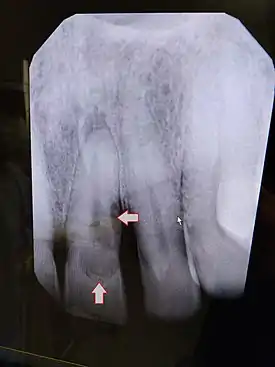

X-Ray of affected tooth (incisor 9, left).

The pathophysiology of root resorption is not completely understood. It is postulated that osteoclasts are the cells responsible for the resorption of the root surface.[7] Osteoclasts can break down bone, cartilage and dentin.[8]